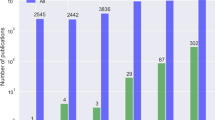

In contrast, most publically available medical image datasets have tens or hundreds of cases, and datasets with more than 5000 well-annotated cases are rare. In the USA, individual healthcare institutions may have 103 up to rarely 107 of an exam type. These common radiology exam types, for example, chest radiographs, unenhanced brain CTs, mammograms, and abdominal CTs, are often high-dimensional data due to variations in pathology, technique, radiology interpretation, patient population, and clinical setting.